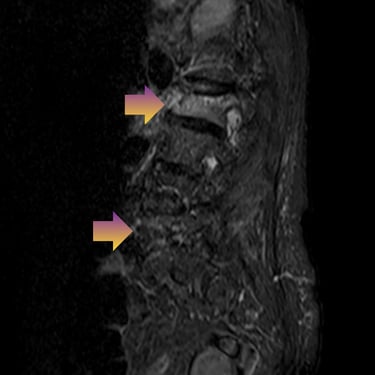

🧠Compresión medular cervical y dorsal: tratamiento mediante artrodesis y descompresión nerviosa.

La compresión medular cervical y dorsal es una patología grave que puede ocasionar déficit neurológico progresivo. La descompresión quirúrgica asociada a artrodesis vertebral permite liberar la médula espinal y estabilizar la columna, mejorando la función neurológica y evitando el deterioro clínico en pacientes adecuadamente seleccionados.